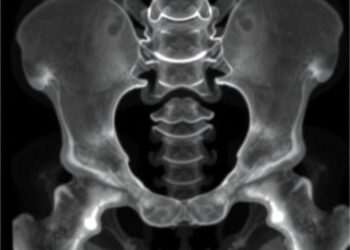

Directional Asymmetry in Acetabulum: Age Estimation Insights

In a groundbreaking exploration that challenges long-standing assumptions in forensic anthropology, new research has brought attention to the phenomenon of ...